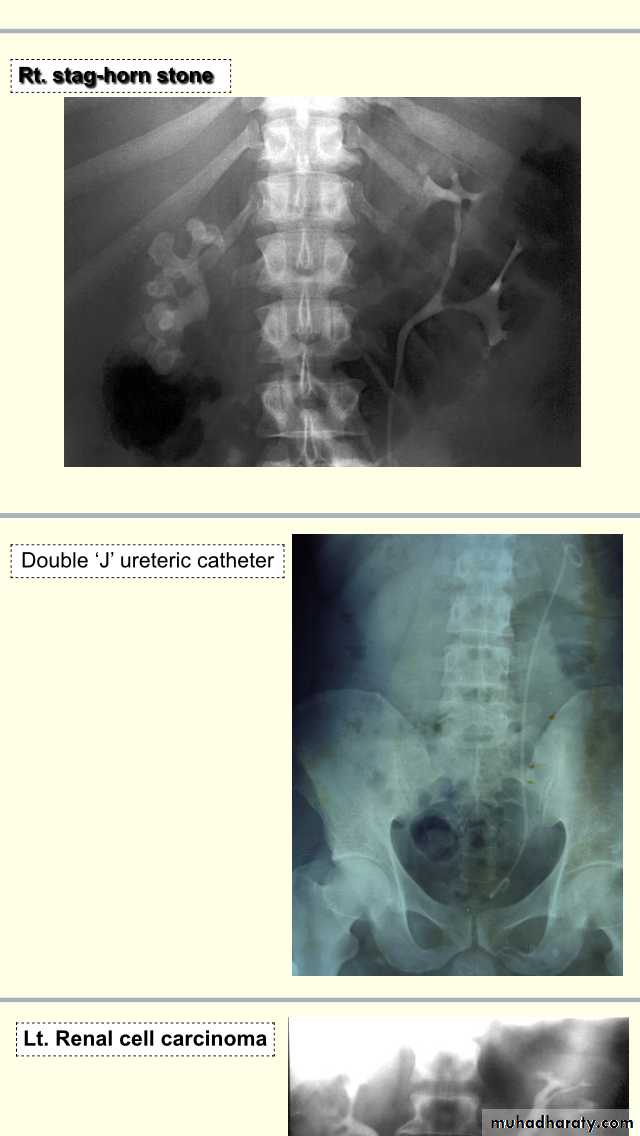

Description :-plain xray of abdomen,,showing longitudinal Radioapque shadow extends from upper part of lt urter to bladder used To divert the urine internally, to drain the upper UT,after surgeries of UT.Description :- IVU in pt with renal mass,compression of calyces of lt kidney , eating of calyces by the tumour , soft tissue mass +loss of lower calyces(eating of lower calyces).